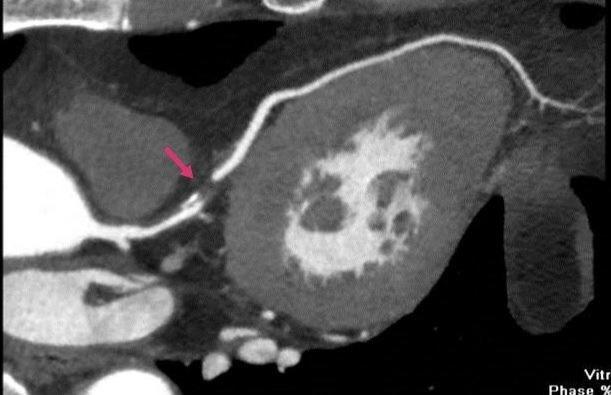

箭头所指部位为血流阻断位置

冠脉CT和冠状动脉造影:比较直观的检查是冠脉CT和冠状动脉造影。需要注射造影剂,来观察冠状动脉的形态和血流,这是目前诊断冠心病的金标准。通过造影剂在冠状动脉的显影,可以看到冠状动脉有没有畸形、冠状动脉有没有斑块和狭窄,狭窄的程度如何。如果狭窄程度超过85%,则需要尽快行冠状动脉内支架植入术。这种方法属于微创手术,技术成熟,安全性很好,可迅速改善患者心肌的缺血症状。全动脉发生病变时,也可以考虑冠状动脉搭桥手术。